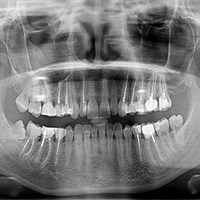

Comprehensive exams and professional hygiene treatments at our Frisco, TX practice start off with an assessment of your dental record. Someone on our team might also talk with you about any oral problems or cosmetic issues you have to learn more about your overall dental health. At certain routine appointments, a set of advanced x-rays may be taken to give Dr. Shardha an overall picture of the health of your enamel and jawbone. He may then screen for cancer of the mouth, check the balance of your bite and jaw joints, and assess your teeth for trauma and the wear of any dental appliances. A periodontal assessment can also be carried out to locate possible areas of gum disease.